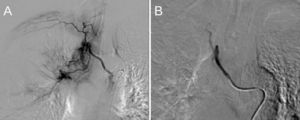

The patient improved after 24h in the prone position, and was extubated 5 days after admission. He was treated with high-flow nasal cannula (HFNC) until the seventh day, when he gradually developed tachypnoea together with intense abdominal pain with guarding in the right upper quadrant. He was re-intubated due to clinical and blood gas worsening with PaO2 65mmHg and PaCO2 30mmHg. Biliary pathology was suspected, so an urgent CT scan was performed, which showed acalculous cholecystitis (Fig. 1), massive bilateral PE and ischaemic colitis. The patient developed septic shock, probably of biliary origin, with growth of Enterobacter aerogenes in peripheral blood cultures, and required infusion of norepinephrine at 0.3mcg/kg/min. The infection was controlled by ultrasound-guided percutaneous cholecystostomy and ertapenem 1g/24h. He also received an anticoagulant (enoxaparin 1mg/kg/12h) for PE. Fourteen days after admission, and after improvement of inflammatory parameters and withdrawal of norepinephrine, he was extubated with PaO2/FiO2 >250; HFNC therapy was maintained. The patient had significant muscle weakness. On the 17th day of admission, he presented lower gastrointestinal bleeding in the form of haematochezia and haemodynamic instability, for which he was re-intubated and norepinephrine infusion 0.2mcg/kg/min was restarted. An urgent CT scan showed ischaemic colitis with no active bleeding or perforation. On the 19th day of admission a tracheotomy was performed. After weaning procedures, he was disconnected from mechanical ventilation on the 34th day of admission. The patient is still in the CCU, receiving conventional oxygen therapy through the tracheostomy and intensive physiotherapy sessions.